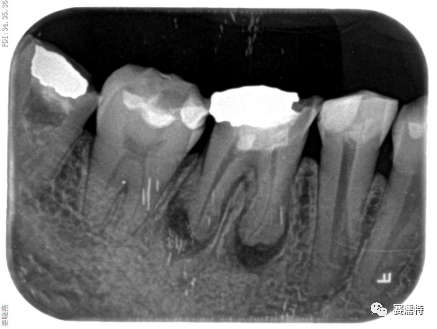

祝自洋老師案例

張云鳳老師案例

張凈玉老師案例

喻剛老師案例

楊艷老師案例

楊超老師案例